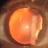

- coloboma

- MEHUL SHAH

- Photo slit lamp biomicroscope

- 35-year-old male presented with diminished vision. On examination he was having nuclear sclerosis and lens coloboma.